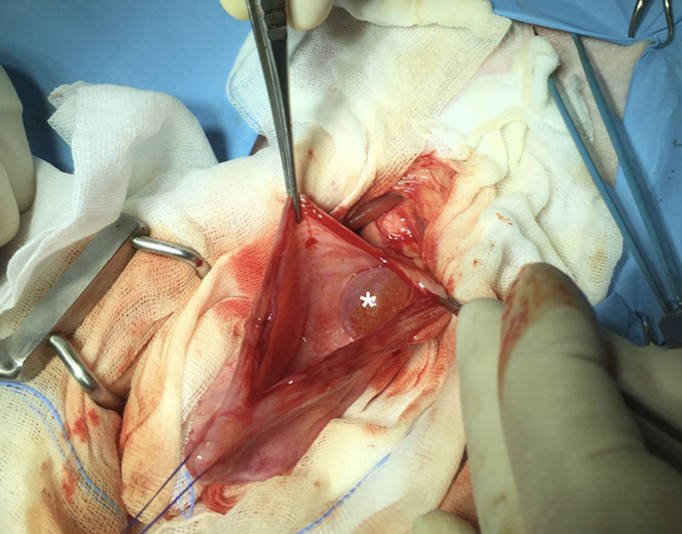

방광을 열어서 보면

이런식으로 방광내부에 물주머니처럼 보일 수 있다.